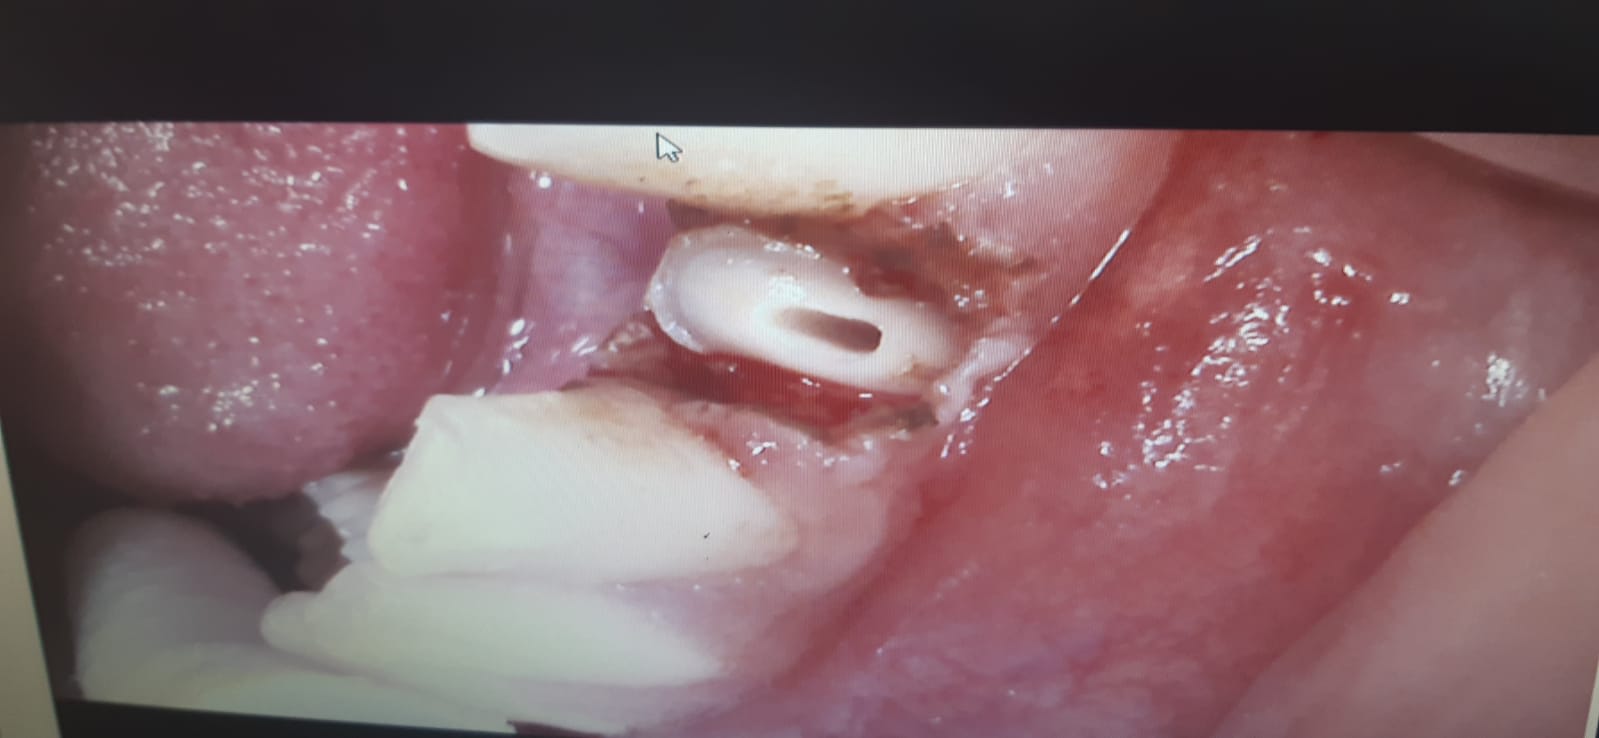

suite à une partie de foot, un gamin de 16 ans arrive avec 31,41 fracturées.

en urgence j'ai traité la 31, qui avait sa partie coronaire très mobile.

J'ai mis la photo pour que vous puissiez juger de l'ampleur de cette cassure.

extraction partie coronaire,dévitalisation,et remise en plan du pan fracturé avec pivot.

je compte faire l'autre samedi(élongation coronaire? sur 41)